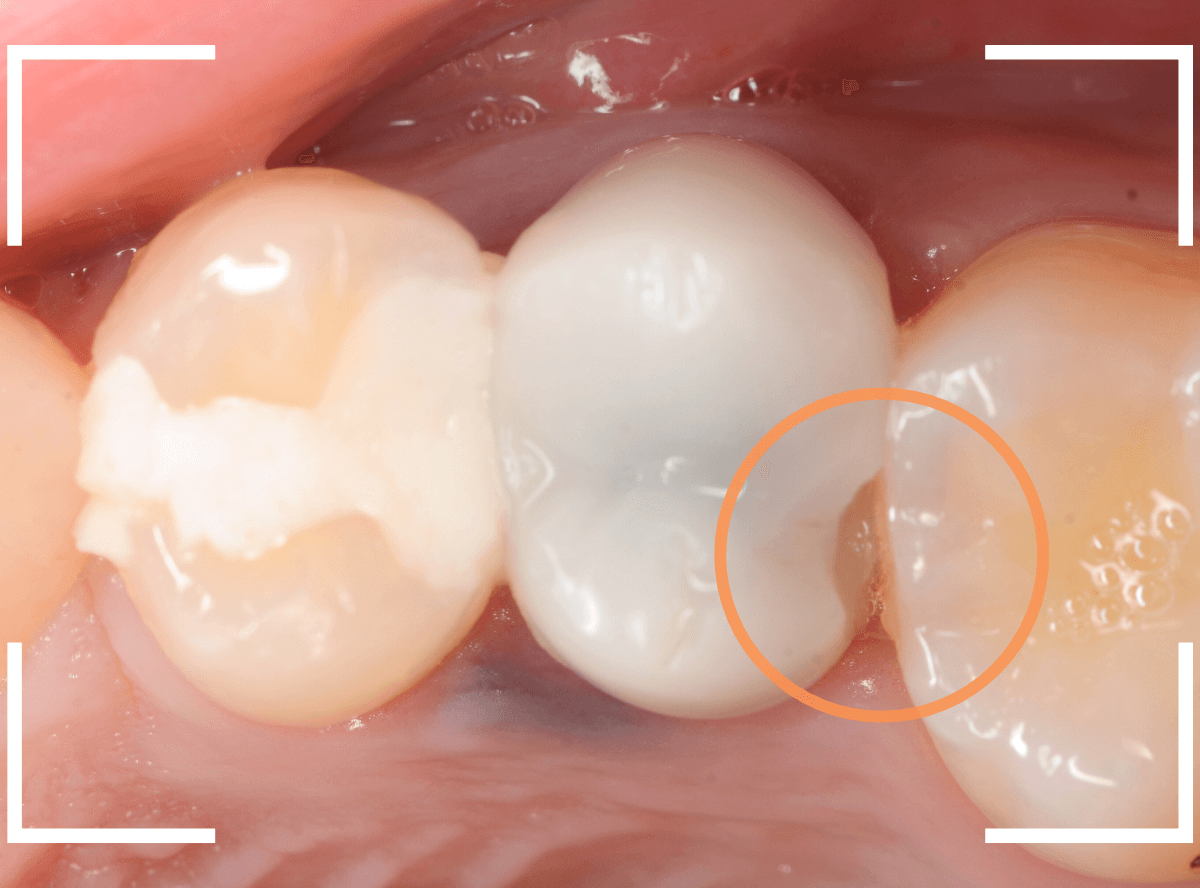

過去に治療したセラミック・インレーが不適合になっているのが、レントゲン写真で見つかりました。

初見では特に問題なかったのですが。。。

後ろの歯とのすき間の部分が欠けてしまったのか、不適合になり、中で虫歯が進行しているように見えます。

初めて来院する患者さんや、治療してから年月が経っている患者さんは、定期的にレントゲン写真で確認する事は大事ですね。

セラミックを外して、虫歯を処置したところです。

幸い、中で大きな虫歯になってはおらずホッとしましたが、セラミック・インレーで作り直すのに支えになるエナメル質の部分が薄く、早期に脱落や破折する可能性がある事、また、手前とのすき間に物がつまりやすくなってきたという訴えもありましたので、今回はさし歯(クラウン)に置き換える事になりました。